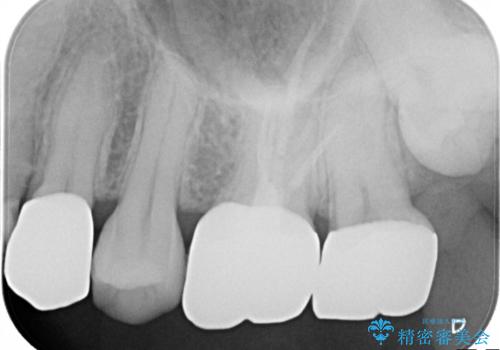

当院の治療は虫歯を除去した後、オールセラミッククラウンによる修復治療を行いました。

虫歯をきちんと除去した状態で最終修復物を入れるため、再治療のリスクを減らす事ができます。